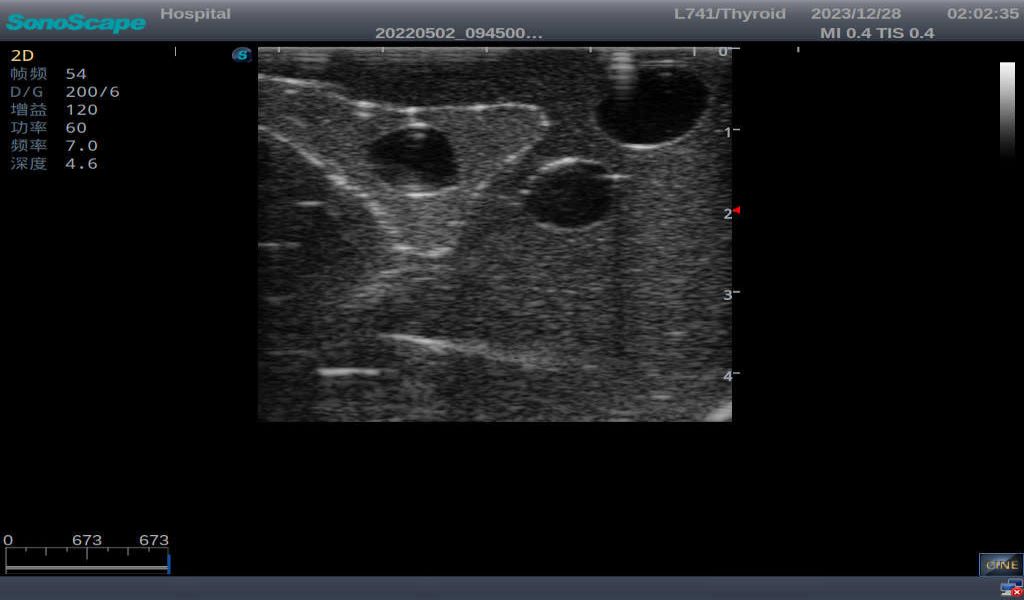

3)       It comes with four (4) thyroid modules and can show five (5) ultrasonic images: normal thyroid, thyroid adenoma, thyroid cancer, nodular goiter, thyroid cyst

Thyroid cyst, which fluid area, dark and echo-free area can be seen